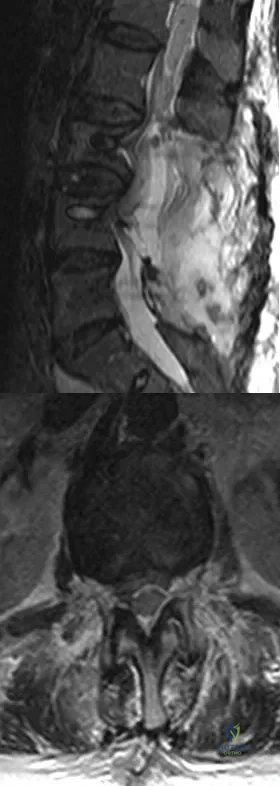

A 78-year-old woman undergoes her third lumbar decompression and fusion from L3 to L5 without complication. On the morning of postoperative day 3, examination reveals painless, flaccid weakness of both lower extremities. She also has an absent bulbocavernous reflex and a mild saddle paresthesia. MRI scans of the lumbar spine are shown in Figures 26a and 26b. What is the most appropriate management at this time?